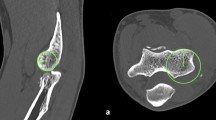

CT standard planes and determination of humeral shaft axis. The determination of the humerus shaft axis as applied for defining the standard planes is described in the section ‘humerus shaft axis’ and is depicted in this figure (A). The determination of the coronal humerus shaft axis (B) is achieved via the same approach as described for the sagittal view. The ‘distal point’ is defined as the most volar location on the trochlea in the sagittal view and the most lateral location on the lateral epicondyle in the coronal view and serves for determination of the sagittal distance. Red line: axial plane, bisects the trochlea in the sagittal view. Yellow line: coronal plane, humerus shaft axis in the sagittal view and parallel to the joint surface (dashed yellow line) in the axial view (C). Blue line: sagittal plane, humerus shaft axis in the coronal view. Grey dashed line: sagittal distance. Green dashed line: connection of point 1 and 2. Circle: trochlea surface (color figure online)

The coronal plane and is adjusted parallel to the joint line in the axial view (Fig. 1C) and as a bisecting line of the trochlea in the sagittal view (Fig. 1A). In the sagittal view (Fig. 1A), the coronal plane parallels the longitudinal axis of the humerus shaft. The sagittal plane is adjusted parallel to the longitudinal axis of the humerus shaft in the coronal view (Fig. 1B). In the axial view, the coronal and sagittal plane are orthogonal to each other, whereas in the coronal view, the axial and sagittal plane and in the sagittal view, the coronal and axial plane are orthogonal to each other.

Humerus shaft axis

The humerus shaft axis was defined using a ‘centerline by four points’ in the sagittal and coronal view using IMPAX EE software (AGFA Health Care, Mortsel, Belgium). The four points were adjusted according to a standardized method (Fig. 1A).

Sagittal view: Point 1 was defined as the most proximal point on the volar outer cortical surface of the humerus shaft. Point 2 was adjusted perpendicular to the middle of the sagittal distance which was defined as the distance between point 1 and the most volar point on the trochlea (distal point). Point 3 was adjusted on the dorsal outer cortical surface opposite to point 1 and perpendicular to a connecting line between point 1 and point 2. Point 4 was adjusted on the dorsal outer cortical surface opposite to point 2 and perpendicular to a connecting line between point 1 and point 2.

Coronal view: Point 1 was defined as the most proximal point on the lateral outer cortical surface of the humerus shaft. Point 2 was adjusted perpendicular to the middle of the distance between point 1 and the most lateral point of the lateral epicondyle (distal point). Point 3 and point 4 were located on the medial outer cortical surface of the humerus and were adjusted as described for the sagittal view.